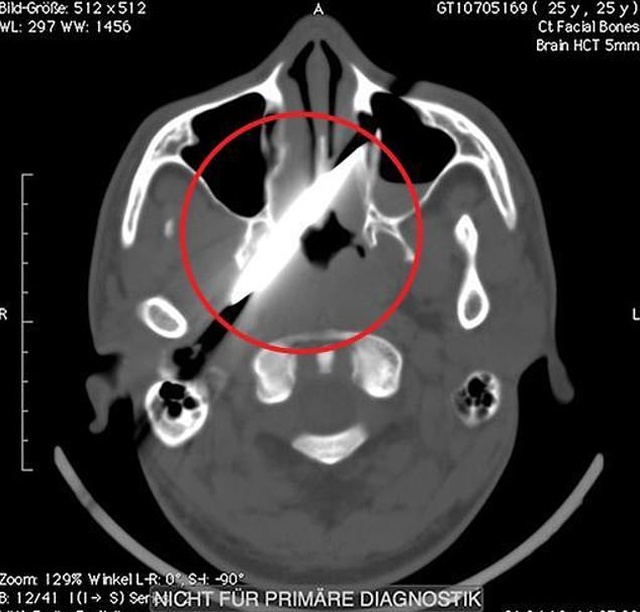

Когда на утро к нему приехали друзья, они уговорили парня обратиться к врачам. Так как он не помнил, что с ним произошло, он лишь пожаловался докторам на сильную головную боль, которая проявлялась только при ходьбе. Пострадавшему пришлось сутки ждать, пока освободится койка в госпитале, а затем еще двое суток, пока ему сделают рентгенографию кровеносных сосудов головы. Хоть в это и верится с трудом, рентген показал, что ни одна из крупных артерий не была повреждена.

Операция состоялась только на четвертый день после происшествия. В ней принимали участие офтальмологи, отоларингологи, челюстно-лицевые хирурги и нейрохирурги. Врачи смогли без повреждений извлечь нож и головы пациента, но затем им пришлось временно зашить ему глаз. На данный момент жизни парня ничего не угрожает.